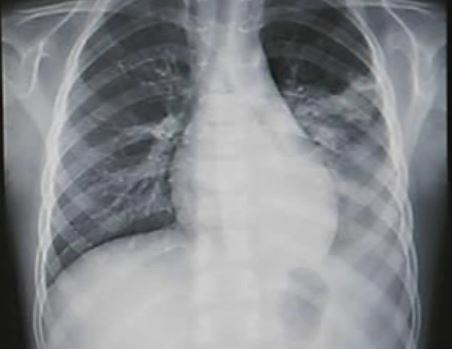

RSV의 가장 큰 문제는 생후 6개월 미만 영아에게 특히 위험하다는 점입니다. 나이가 어릴수록 증상이 심하게 나타나며, 심한 경우 입원 치료가 필요합니다. 실제로 제 아이는 돌 이후 폐렴으로 입원했을 때, 같은 병실과 옆 병동에 RSV로 입원한 신생아와 영아들이 정말 많았습니다. 특히 미숙아나 선천성 심장질환이 있는 고위험군 아기들은 RSV 감염 시 호흡곤란으로 중환자실 치료를 받아야 하는 경우도 있습니다(출처: 질병관리청).